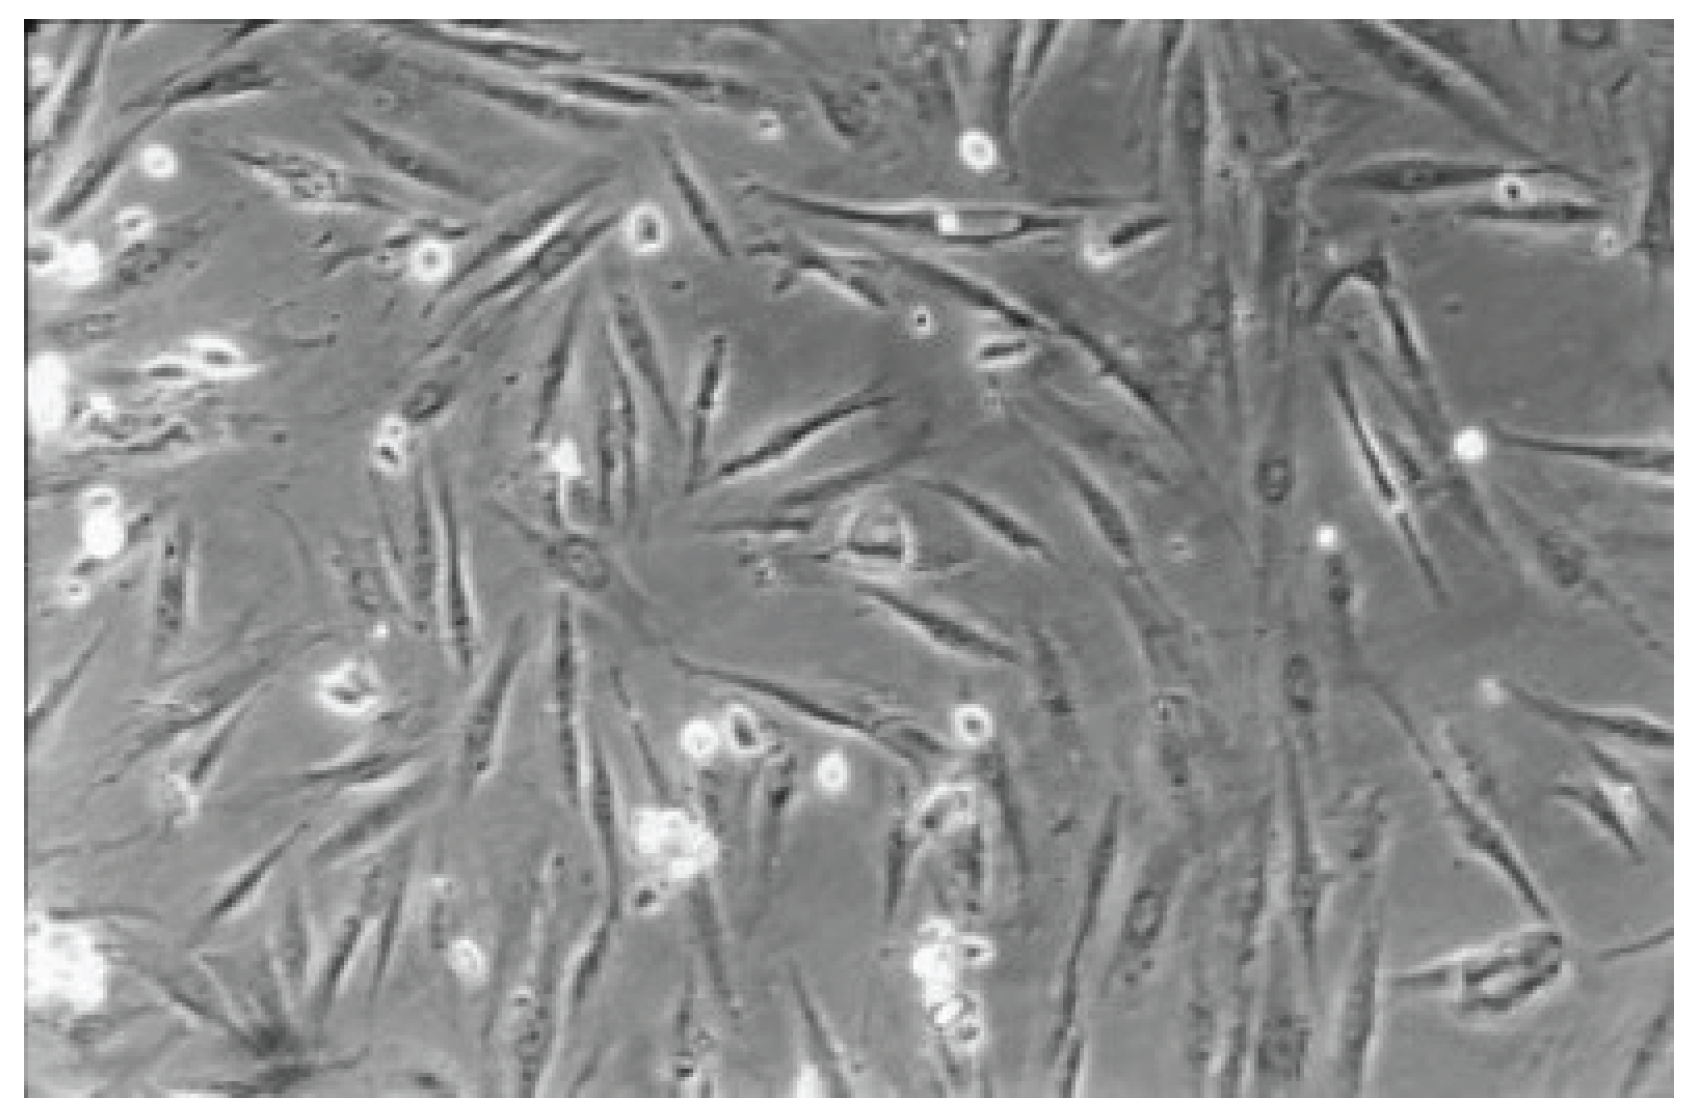

The qualitative evaluation is shown in Table 2, Table 3, Table 4, Table 5, Table 6 and Table 7. Figure 6, Figure 7, Figure 8, Figure 9, Figure 10, Figure 11 and Figure 12 depict the characteristic appearance of the cell cultures in the influence of the different dentin adhesive materials. The morphological phenotype of this cell line is characterised by spindle-shaped, long cells derived from the gingiva (HGPFC—human gingival primary fibroblast cells) representing human primary fibroblasts (pMF).

Figure 6. The cell control (No. 7) presents a regular dense lawn of fibroblasts with characteristic long cells after 48 hours (100-fold magnification).